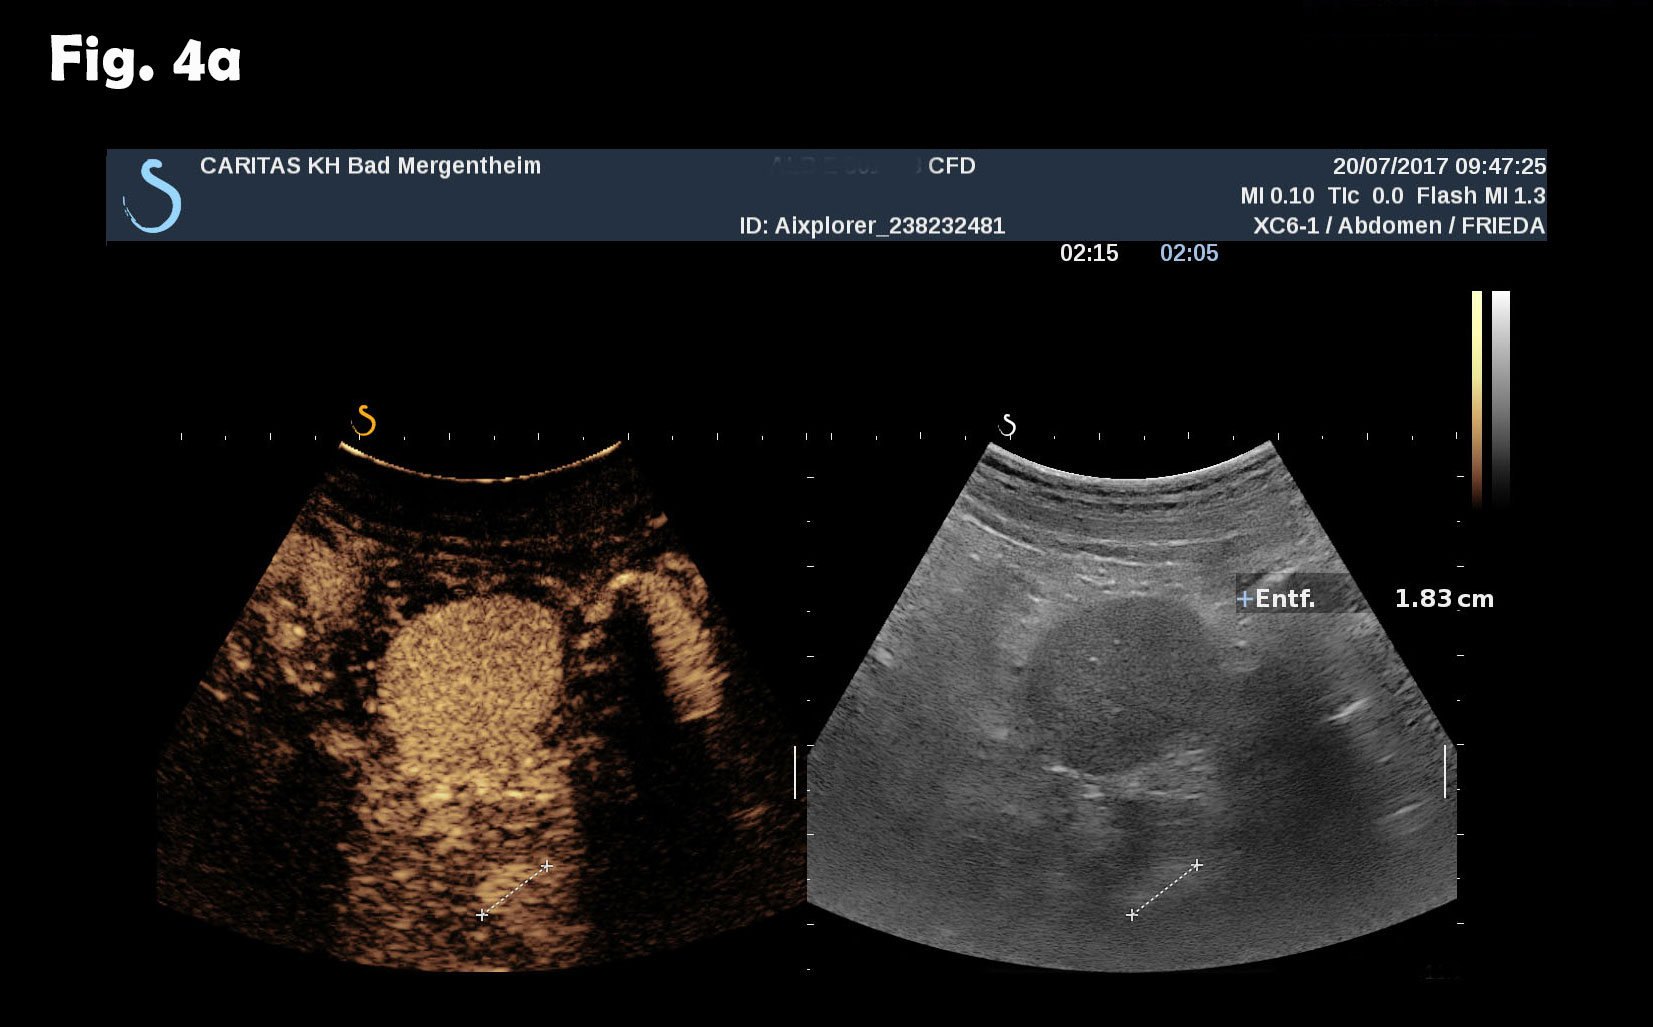

Computed tomography of the chest revealed pneumonic infiltration but was otherwise normal. The endoscopic examination of the upper and lower gastrointestinal tract was normal. Contrast enhanced ultrasound (CEUS) showed arterial and late phase enhancement lasting more than 5 minutes in all examined nodules. After Biopsy the ultrasound examination was performed showing multiple almost echofree but also echogenic round and oval shaped focal peritoneal masses with a size of up to 46 mm [Figure 2-4].

Figure 4: At different abdominal locations more echogenic round oval lesions upt to 30 mm were identified by ultrasound. The lesions were best depicted during the late phase enhancement behind the accessory spleen next to the lesion shown in figure 2 (a) and elsewhere in the abdomen (b). The Figure 3c represents the CT finding shown in figure 1.